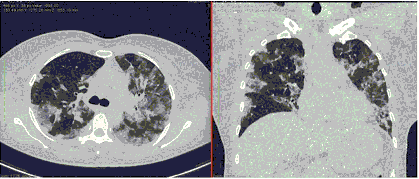

- Изменения при КТ (рентгенографии), типичные для вирусного поражения (объем поражения минимальный или средний; КТ 1-2)

- Изменения в легких при КТ (рентгенографии), типичные для вирусного поражения (объем поражения значительный или субтотальный; КТ 3-4)

- Изменения в легких при КТ (рентгенографии), типичные для вирусного поражения критической степени (объем поражения значительный или субтотальный; КТ 4) или картина ОРДС.

КТ имеет высокую чувствительность в выявлении изменений в легких, характерных для COVID-19. Применение КТ целесообразно для первичной оценки состояния ОГК у пациентов с тяжелыми прогрессирующими формами заболевания, а также для дифференциальной диагностики выявленных изменений и оценки динамики процесса. КТ позволяет выявить характерные изменения в легких у пациентов с COVID-19 еще до появления положительных лабораторных тестов на инфекцию с помощью МАНК. В то же время, КТ выявляет изменения легких у значительного числа пациентов с бессимптомной и легкой формами заболевания, которым не требуется госпитализация. Результаты КТ в этих случаях не влияют на тактику лечения и прогноз заболевания при наличии лабораторного подтверждения COVID-19. Поэтому массовое применение КТ для скрининга асимптомных и легких форм болезни не рекомендуется.

3. Применение лучевых методов у пациентов с симптомами ОРВИ легкой степени тяжести и стабильном состоянии пациента, возможно только по конкретным клиническим показаниям, в том числе при наличии факторов риска, при условии достаточных технических и организационных возможностей. Методом выбора в этом случае является КТ легких по стандартному протоколу без внутривенного контрастирования или РГ при ограниченной доступности КТ. Использование УЗИ в этих случаях нецелесообразно.

5. Рекомендовано проведение лучевого исследования пациентам при среднетяжелом, тяжелом и крайне тяжелом течении ОРИ с целью медицинской сортировки, оценки характера изменений в грудной полости и определения прогноза заболевания:

- выполнение КТ легких без внутривенного контрастирования в стационарных условиях или в амбулаторных - при показаниях к госпитализации;